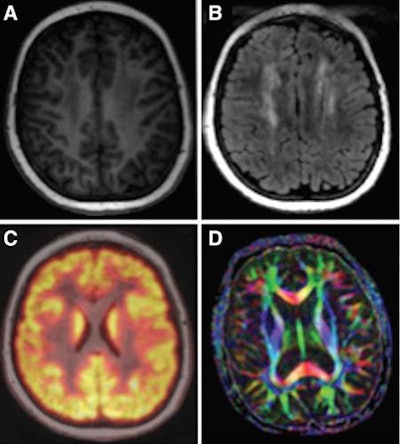

PET/MRI

Compared with 3D printing, PET/MRI is a relatively mature technology. But it continues to capture the imagination of radiology with its powerful fusion of functional information from PET with anatomical detail from MRI.

In 2017, researchers produced papers that demonstrated their effort to make the expensive technology more suitable for routine clinical imaging. For example, in August a group from Stanford University revealed a protocol for performing PET/MRI in a single session for pediatric cancer patients -- making the studies more tolerable. And in April, a German group found that using a lower dose of FDG didn't compromise the diagnostic quality of the PET component; meanwhile, another German group found PET/MRI to be no better than PET/CT for evaluating head and neck cancer.

At RSNA 2016, a group from NYU Langone Medical Center found that including the head in a whole-body PET/MRI scan uncovered more incidental findings that might have been missed -- with lower radiation dose than PET/CT. And a group from New York University found the modality to be well-suited for finding distant metastases in patients with breast cancer.

In the coming year, look for researchers to continue to refine PET/MRI to make it more economical and clinically useful, particularly for oncology applications.